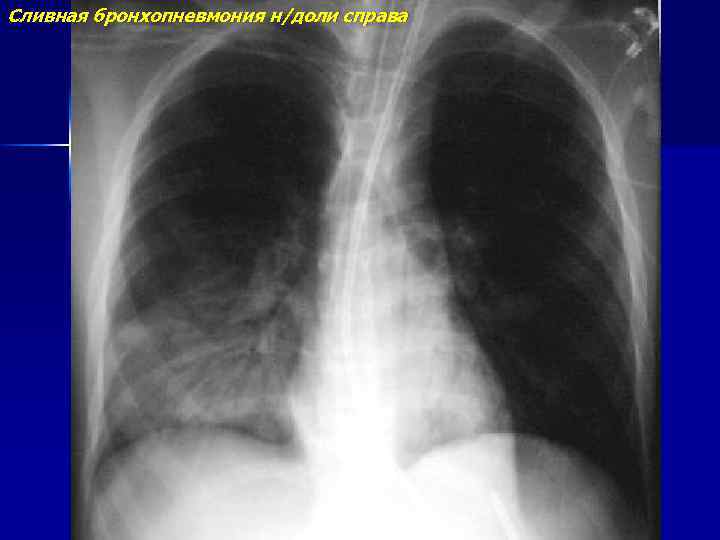

Сливная бронхопневмония н/доли справа

Двухстороняя сливная бронхопневмония